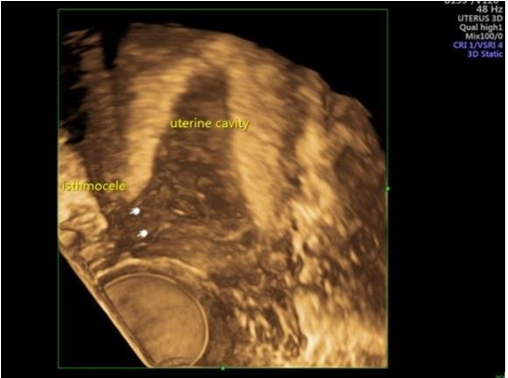

Management of Isthmocele: A Case Report